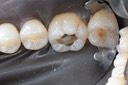

Joe Cha #29 pre-op

Joe Cha #29 prep